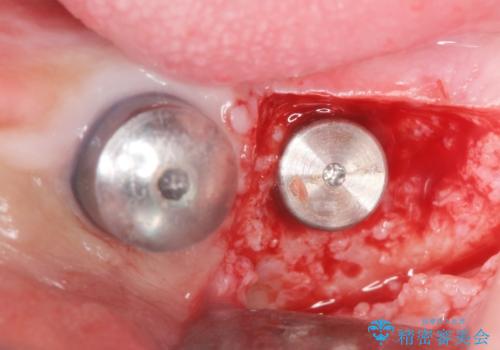

禁煙指導と歯周病治療後、左下臼歯部(左下467埋入)のインプラント治療を行いました。

インプラントの埋入は、抜歯後4ヶ月程度骨の治癒を待ったり、骨が少ない部分に関しては骨増生を行ったりして順次行いました。

インプラントの種類:スプラインツイスト(HAコーティング)

固定様式:スクリュー固定